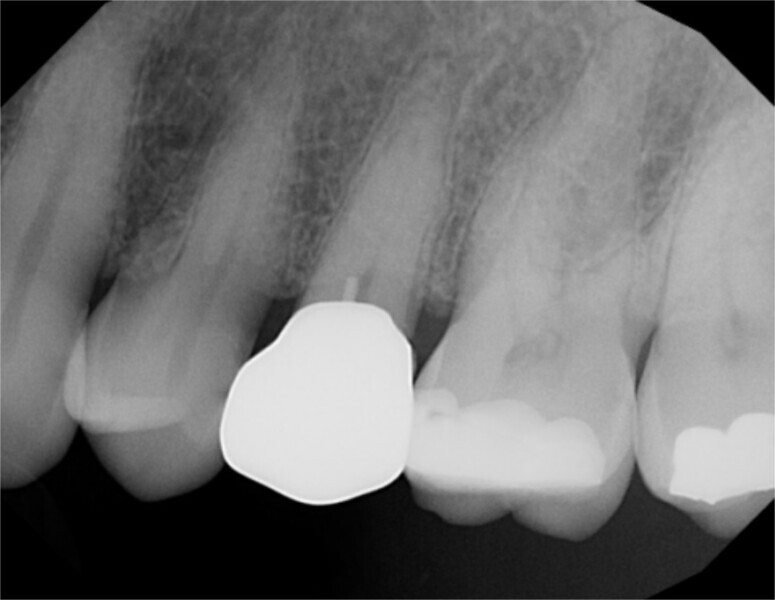

The patient was seen on recall at four weeks after restoration, and a periapical radiograph was taken (Fig. 9). No periapical radiolucency was noted, and the patient continued to report a lack of sensitivity to temperature or occlusion, indicating successful laser treatment of the pulpal exposure.

Fig. 9: Periapical radiograph taken four weeks after restoration placement, demonstrating an absence of periapical pathology.